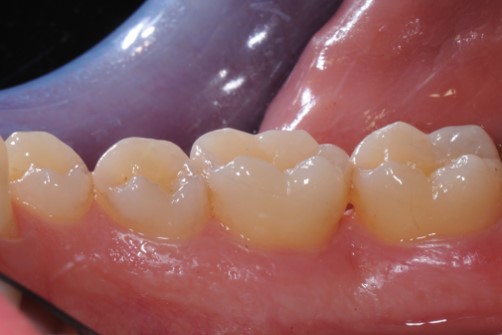

Contained intrabony defect treated using Straumann® Emdogain® - Kasaj

Radiographic view before periodontal regenerative therapy with Straumann® Emdogain®. A deep intrabony defect appeared mesially and distally on the left mandibular first premolar. Pre-surgical probing measured 8 mm. The defect morphology presented as well-contained.